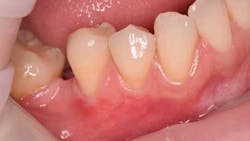

This 35-year-old female with a noncontributory medical history presented to private practice with a chief complaint of “a possible crack on the upper right canine and generalized teeth sensitivity when brushing.” She was missing the upper left and lower right first molar. Tooth No. 30 was lost at the age of 9, and the second molar, tooth No. 31, was mesially inclined and drifted into the area of No. 30. Both horizontal and vertical ridge deficiency was noted, and inadequate space for an implant was present. Her lower right quadrant demonstrated Class I and II Miller recessions with less than 2 mm of keratinized tissue (figure 1).